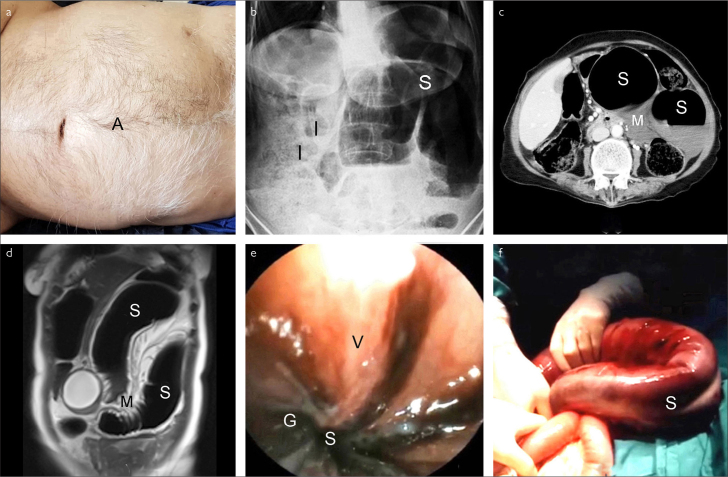

In SV, abdominal pain/tenderness, obstipation, and asymmetrical abdominal distention (Figure 1a), which are described as the volvulus triad, are observed in 52%-99% of patients.1,3 In our evaluation, these clinical features were found in 98.9%, 96.6%, and 92.4% of patients, respectively. Other clinical features are vomiting, hyperkinetic or hypokinetic bowel sounds, empty rectum or melanotic stool, and shock.1,3 In endemic regions, the determination of the abovementioned features in a middle aged or elderly man is generally suggestive of SV.3 Plain abdominal X-ray radiography demonstrating an omega-shaped sigmoid colon with small intestinal air-fluid levels is diagnostic in 25%-90% of patients (Figure 1b)1,3; this was observed in 68.2% of our patients. Nevertheless, the diagnostic values of computerized tomography (CT) and magnetic resonance imaging (MRI) are generally reported to be over 90%. In CT and MRI, the pathognomonic finding of SV is mesenteric whirl sign arising from rotated sigmoid mesentery in addition to the dilated sigmoid colon and small intestinal air-fluid levels (Figures 1c, 1d).3 In our evaluation, the diagnostic accuracy of CT and MRI were 97.3% and 95.6%, respectively. Endoscopic sign of SV is a spiral torsion of the lumen, usually 20-30 cm from the anal verge (Figure 1e). Endoscopy is diagnostic in 76%-100% of patients3; this was observed in 98.7% of our patients. When CT, MRI, or endoscopy are not used, SV is easily misdiagnosed as an intestinal obstruction, which generally requires an emergency laparotomy.1,3